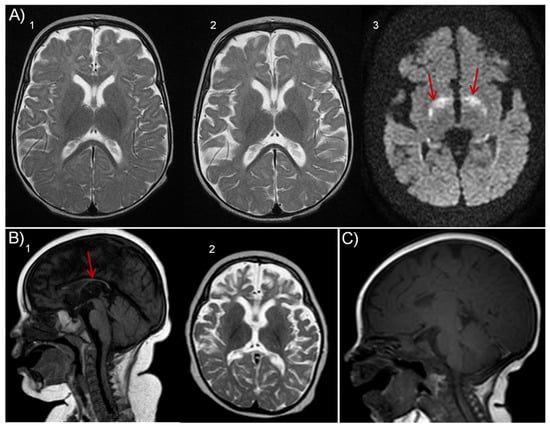

| MRI findings | Yes Frontotemporal atrophy | Yes Thin corpus callosum | Yes Thin corpus callosum Progressive frontotemporal atrophy | Yes Thin corpus callosum Progressive atrophy Hypomyelination | |